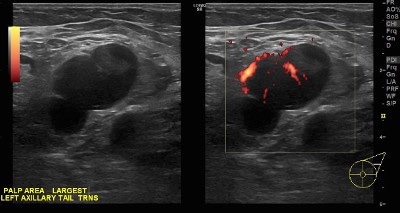

👉When a lymph node is completely replaced with metastatic cancer, it will be rounded, hypoechoic, and the hilum will be completely obliterated. (Image).

👉Before the node reaches the stage of complete replacement, it can have an asymmetric, thickened cortex, with an eccentric hilum (Image).

👉Finally, a reactive node has blood supply on Doppler examination through a single hilum, whereas metastatic nodes tend to have multiple transcapsular vessels (Image).